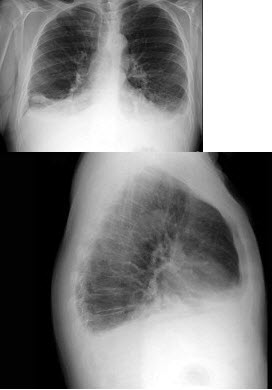

40、单项选择题

女,67岁,咳嗽1周,有甲状腺癌史,结合胸片,最可能的诊断()

A.甲状腺癌肺转移

B.粟粒型肺结核

C.尘肺

D.结节病

E.肺炎